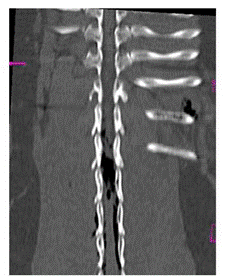

Se realizó un estudio de tomografía helicoidal multicorte (TEM) de columna Tora-co-lumbar realizado en posición supina, con adquisición volumétrica de 1,0 mm y cortes de 5 mm desde T8 a S1. En la TEM se identificó alineación longitudinal y curvatura de columna toraco lumbosacra anteroposterior de aspecto conservado, sin observarse signos en relación a listesis ni fracturas. Se evidenció aire intrarraquídeo compatible con Neumorraquis y enfisema de partes blandas pre y paravertebrales toraco lumbares, Dicho producía cambios compresivos sobre el cordón medular (Figuras 2-4). Sobre la base de los hallazgos por TEM y el mal pronóstico debido al severo daño neurológico, los responsables del paciente tomaron la decisión de realizar la eutanasia.

El NR puede ser clasificado como interno (intradural) y externo (extradural). El NR externo generalmente no produce alteraciones, sin embargo, el NR interno suele relacionarse con procesos traumáticos encefálicos y es un indicador de lesión grave11. La localización y distribución del aire dentro del canal espinal dependerá del sitio de disección del aire, del volumen de aire intraespinal, de la capacidad del espacio intraespinal y el posicionamiento del paciente. En la NR externa, el aire epidural generalmente se ubica en la región epidural dorsal, ya que es menos resistente debido a la menor cantidad de tejido conectivo, esto al compararlo con la red vascular ventral12. La TEM, es la herramienta de elección para el diagnóstico de esta lesión1. Sin embargo, la diferenciación entre un NR intra y extradural puede ser complicado, por lo que es indispensable realizar el monitoreo del estado neurológico del paciente.